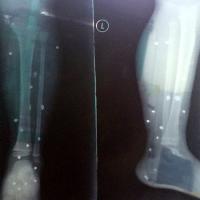

Thông tin ban đầu cho biết cán bộ công an bị thương trong lúc truy bắt cướp là Phó trưởng Phòng Hình sự, Công an tỉnh Hà Tĩnh. Hiện cán bộ công an này đang điều trị tại bệnh viện, vết thương vào phầm mềm ở đùi không nguy hiểm đến tính mạng.